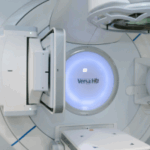

High-energy x-rays or other particles are used in radiation treatment to kill cancer cells. Radiation oncologists are medical professionals that specialize in administering radiation therapy as a cancer treatment. Radiation therapy for breast cancer comes in a variety of forms:

External-beam radiation therapy: This sort of radiation therapy, which is administered from a machine outside the body, is the most popular. This covers both full and partial breast radiotherapy, as well as expedited breast radiotherapy, which might last a few days rather than a few weeks.

Intensity-modulated radiation therapy: An improved method of administering external-beam radiation treatment to the breast is intensity-modulated radiation therapy (IMRT). To more effectively target the tumor and distribute the radiation more uniformly across the breast, the radiation’s intensity is changed. The use of IMRT reduces the radiation dosage, which may reduce the risk of harm to neighboring organs like the heart and lungs as well as certain acute adverse effects like skin peeling during treatment.

Proton therapy: X-rays, commonly known as photon therapy, are used in conventional radiation therapy for breast cancer to destroy cancer cells. A form of external-beam radiation therapy known as proton therapy employs protons rather than x-rays. Protons have the power to kill cancer cells at high energies. Different physical characteristics of protons might make radiation treatment more precise than photon therapy and possibly result in lower radiation dosage. The treatment could help cut down on radiation exposure close to the heart.